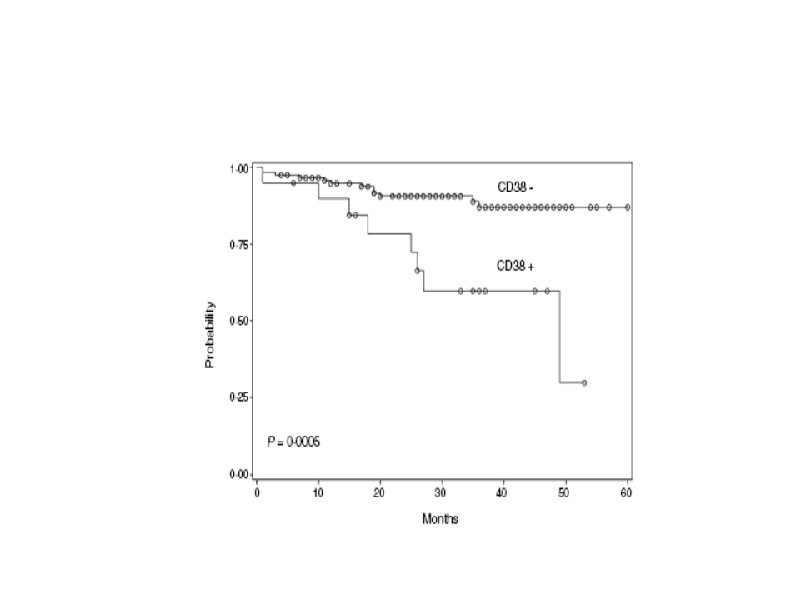

Время удвоения лимфоцитов менее 6 месяцев Время удвоения лимфоцитов более 6 месяцев Стадия на момент диагноза III – IV / C (Rai / Binnet) Возраст менее 65 лет I – II / A Возраст более 65 лет ZAP-70 < 20% Соматическая мутация (-) Соматическая мутация (+) 17 p делеция (p 53 мутация), 13 q делеция 11 q делеция, 12 q трисомия CD 38 (+) CD 38 (-)